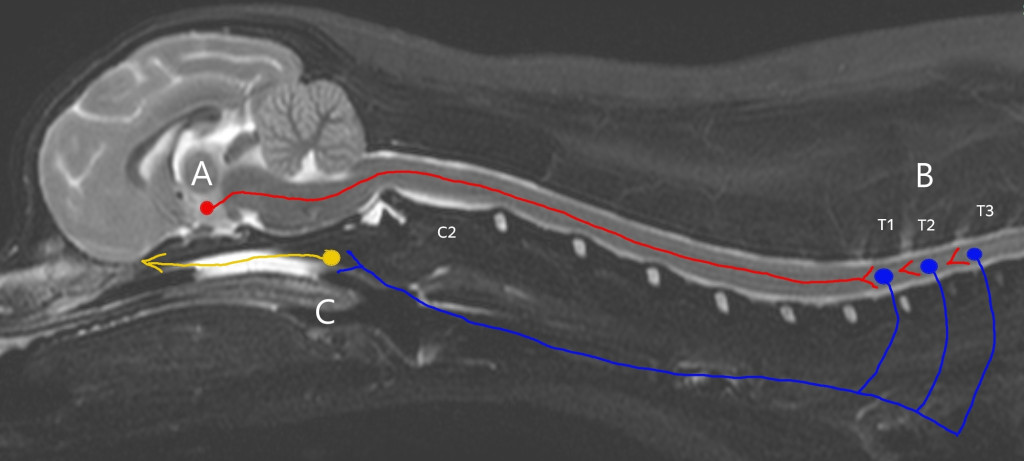

Симпатическая иннервация глаза представляет собой трехнейронную систему. Центральный нейрон, также известный как нейрон первого порядка, располагается в гипоталамусе. Его аксон проходит через ствол мозга и продолжает свой путь в латеральном тектотегментоспинальном (покрышечно-спинальном) тракте, расположенном в латеральном канатике белого вещества спинного мозга12,13,14 (рис. 3). Аксон нейрона первого порядка образует синаптический контакт с преганглионарным нейроном (нейроном второго порядка) в интермедиалатеральном роге серого вещества первых трех грудных сегментов спинного мозга12. Аксон преганглионарного нейрона (нейрона второго порядка) покидает спинной мозг в составе вентральных нервных корешков (Т1, Т2, Т3; рис. 4) и проходит небольшое расстояние в составе спинномозгового нерва, после чего отделяется в виде соединительной ветви (лат. ramus communicans) в месте, где спинномозговой нерв латерально от межпозвоночного отверстия делится на дорсальную и вентральную ветви12,15. Далее соединительная ветвь входит в грудной отдел симпатического ствола, располагающегося вентролатерально по отношению к телам позвонков. Симпатический ствол продолжается краниально в пределах дорсального средостения, проходя через шейно-грудной ганглий, локализованный в области поверхности краниальной доли легкого, и далее к среднему шейному ганглию12,15. При прохождении через оба этих ганглия синаптическая передача не осуществляется (не образует синапсов). На уровне краниальной апертуры грудной клетки (вход в грудную клетку) симпатический ствол объединяется с блуждающим нервом в пределах общего эпиневрия12. Затем вагосимпатический ствол направляется краниально к голове, проходя по латеральной поверхности трахеи, после чего симпатический ствол отделяется от блуждающего нерва и заканчивается в краниальном шейном ганглии12,14. Краниальный шейный ганглий располагается вентромедиально по отношению к барабанной булле, здесь аксон преганглионарного нейрона образует синаптический контакт с телом постганглионарного (третьего порядка) нейрона12. Синаптическая передача в ганглии осуществляется с участием ацетилхолина, который высвобождается преганглионарными телодендриями и связывается с никотиновыми холинергическими рецепторами на теле постганглионарного нейрона12,15.Путь аксонов постганглионарного нейрона описан не столь четко, как путь проксимальных отделов окулосимпатического пути. После выхода аксонов из краниального шейного ганглия они образуют сплетение вокруг внутренней сонной артерии12,15. Часть волокон проходит через барабанную буллу по вентральной поверхности каменистой части височной кости, в то время как другие идут медиальнее буллы, прежде чем войти в полость черепа12,14. Постганглионарные волокна могут также сопровождать внутреннюю сонную артерию и проникать в полость черепа через тимпаноокципитальную щель и сонный канал12,14,16.

A – гипоталамус и нейрон первого порядка; аксон проходит через ствол мозга и далее в латеральном тектотегментоспинальном тракте.

B – первые три грудных сегмента спинного мозга и нейрон второго порядка; преганглионарный аксон покидает спинной мозг, направляется краниально, объединяется с блуждающим нервом и образует вагосимпатический ствол.

C – область среднего уха и нейрон третьего порядка; постганглионарные волокна иннервируют структуры глаза.